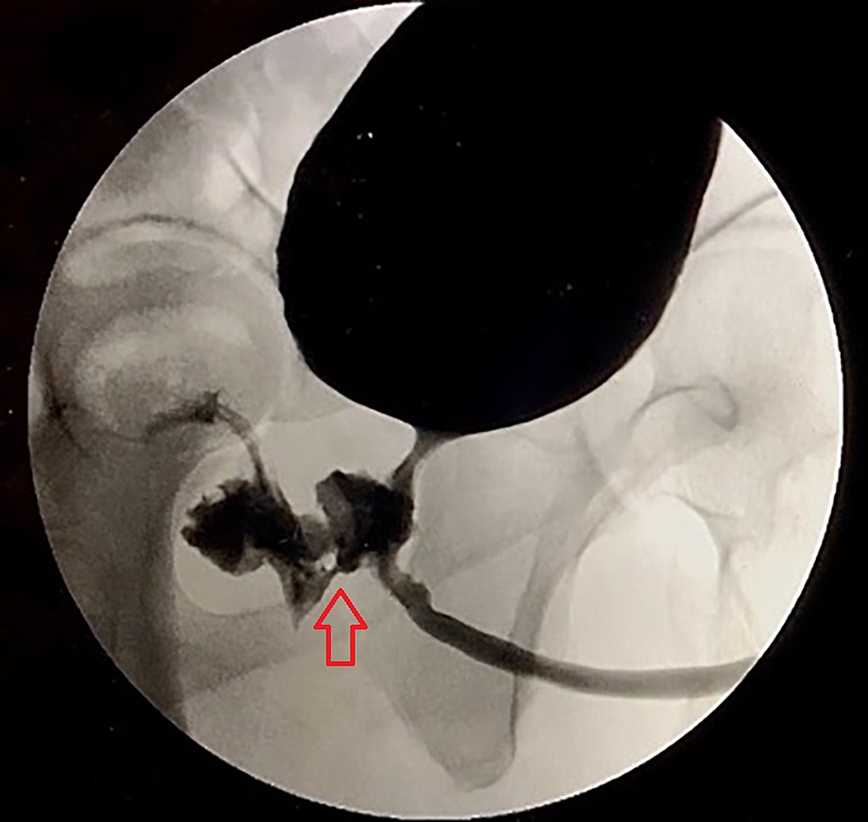

Περαιτέρω δοκιμές επιβεβαίωσαν την ύπαρξη ενός συριγγίου μεταξύ της ουρήθρας και του ορθού, από το οποίο περνούσαν τα διάφορα υγρά και στερεά. Εκτός από την επιδιόρθωση του συριγγίου μέσω χειρουργικής επέμβασης, η ομάδα αναζήτησε πιθανές αιτίες του προβλήματος.